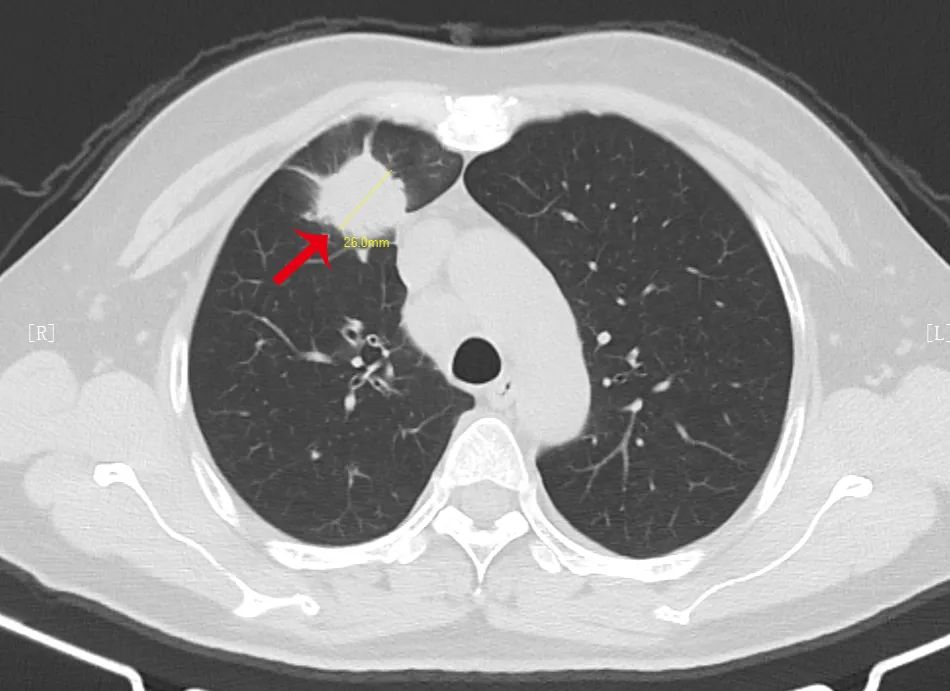

根据肺结节的密度将其分为三大类:实性结节、磨玻璃结节、部分实性结节,密度不一样,高危结节大小的评判标准也不同,>1.5 cm 的实性结节或者>8 mm 的部分实性结节。

长相越是古怪的结节,越需要高度重视,尤其是出现分叶、毛刺、胸膜牵拉、含气细支气管征和小泡征、偏心厚壁空洞等征象。